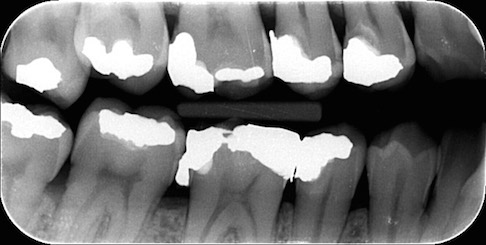

Pravidelná kontrola obnáší kompletní kontrolu zubů a parodontu včetně základních skusových rentgenů. Obsahuje rovněž základní odstranění zubního kamene a pigmentací.